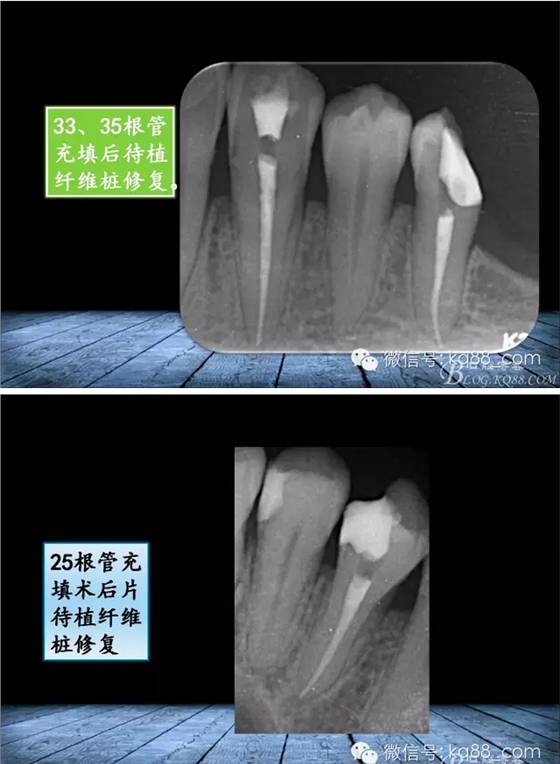

QQ圖片20150817140811.png

QQ圖片20150817140835.png